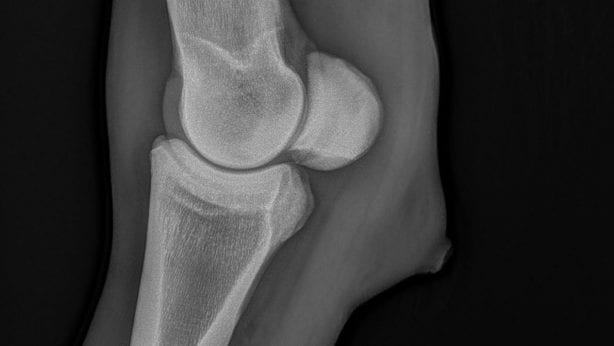

Voor een juiste beeldvorming wordt veelal het röntgenapparaat toegepast. Door middel van röntgenstralen worden foto’s gemaakt van de binnenkant van het lichaam. Op deze manier kan het skelet van het paard, maar organen goed in beeld worden gebracht.

We gebruiken het röntgenapparaat vaak in de orthopedie, wat zich bezighoudt met het onderzoek en behandeling van het bewegingsapparaat. Kreupelheid, fracturen, standsafwijkingen en botontstekingen worden door middel van röntgenonderzoek in beeld gebracht. Daarnaast kunnen we ook aanhechtingsproblemen van pezen en banden, maar ook botafwijkingen zien.